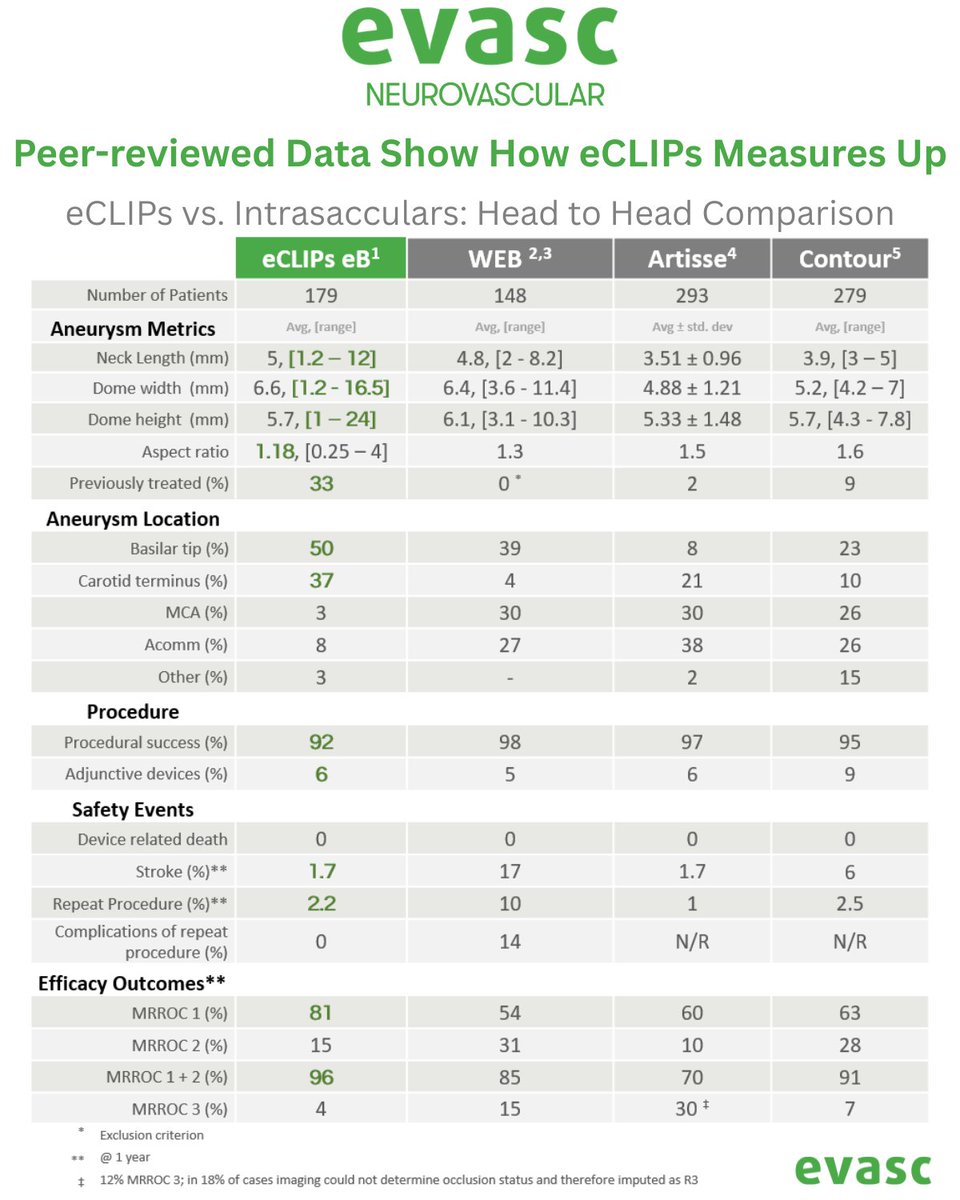

Real-world data confirm #eCLIPs delivers durable, efficient & safe outcomes for #WNBAs — now published in Neurosurgery Publications . Plus: CE/MDR approval & limited launch of our 0.021" compatible eBFD. 📄 Study: bit.ly/4lezYWp 🔗 PR: bit.ly/41oko3f #Neurointervention